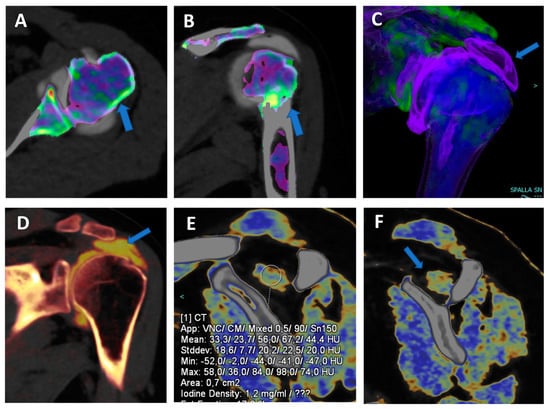

Figure 1.

Recurrent anterior shoulder dislocation in a previously operated patient. By using multiple applications, DECTA can help in the diagnosis of anterior shoulder dislocation, potentially representing a “one-stop one-shop” procedure. A blended virtual 120 kVp axial CTA image (A) shows anterior labral and glenoid rim disruption (arrow). A VNC image on the axial (B) and sagittal (E) planes helps in the evaluation of bone morphology, allowing correct glenoid surface measurement (arrow). In the axial iodine map (C), it is possible to better evaluate the morphology of the anterior labrum (arrow). In the axial BME 2D superimposed image (D), it is possible to recognize edema of the anterior glenoid rim (blue arrow) and subtle edema of the posterior aspect of the humeral head (white arrow), which is consistent with recent recurrent dislocation.

In clinical practice, BME maps reconstructed from VNCa imaging could be employed to detect bone marrow lesions around the imaged joints. Although iodinated contrast material could generate some artifacts in the adjacent areas, the presence of BME can still be visualized. For example, in the case of shoulder trauma with doubtful dislocation, the presence of BME on the posterior aspect of the humeral head may help corroborate the diagnosis of a Hill-Sachs lesion (Figure 1 and Figure 6). In addition, BME around the joint, with or without erosions, can be found in inflammatory diseases such as septic or aseptic arthritis [31,32,33] (Figure 7).